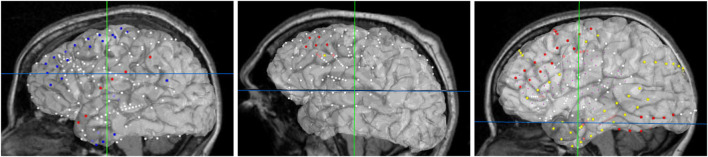

FIGURE 7.

Final browser-based visualization of three different subjects NY704, NY758, NY836 including localization of electrodes on the brain surface. The color of each electrode represents the different attribute (onset, early spread, etc.) for the corresponding seizure type.